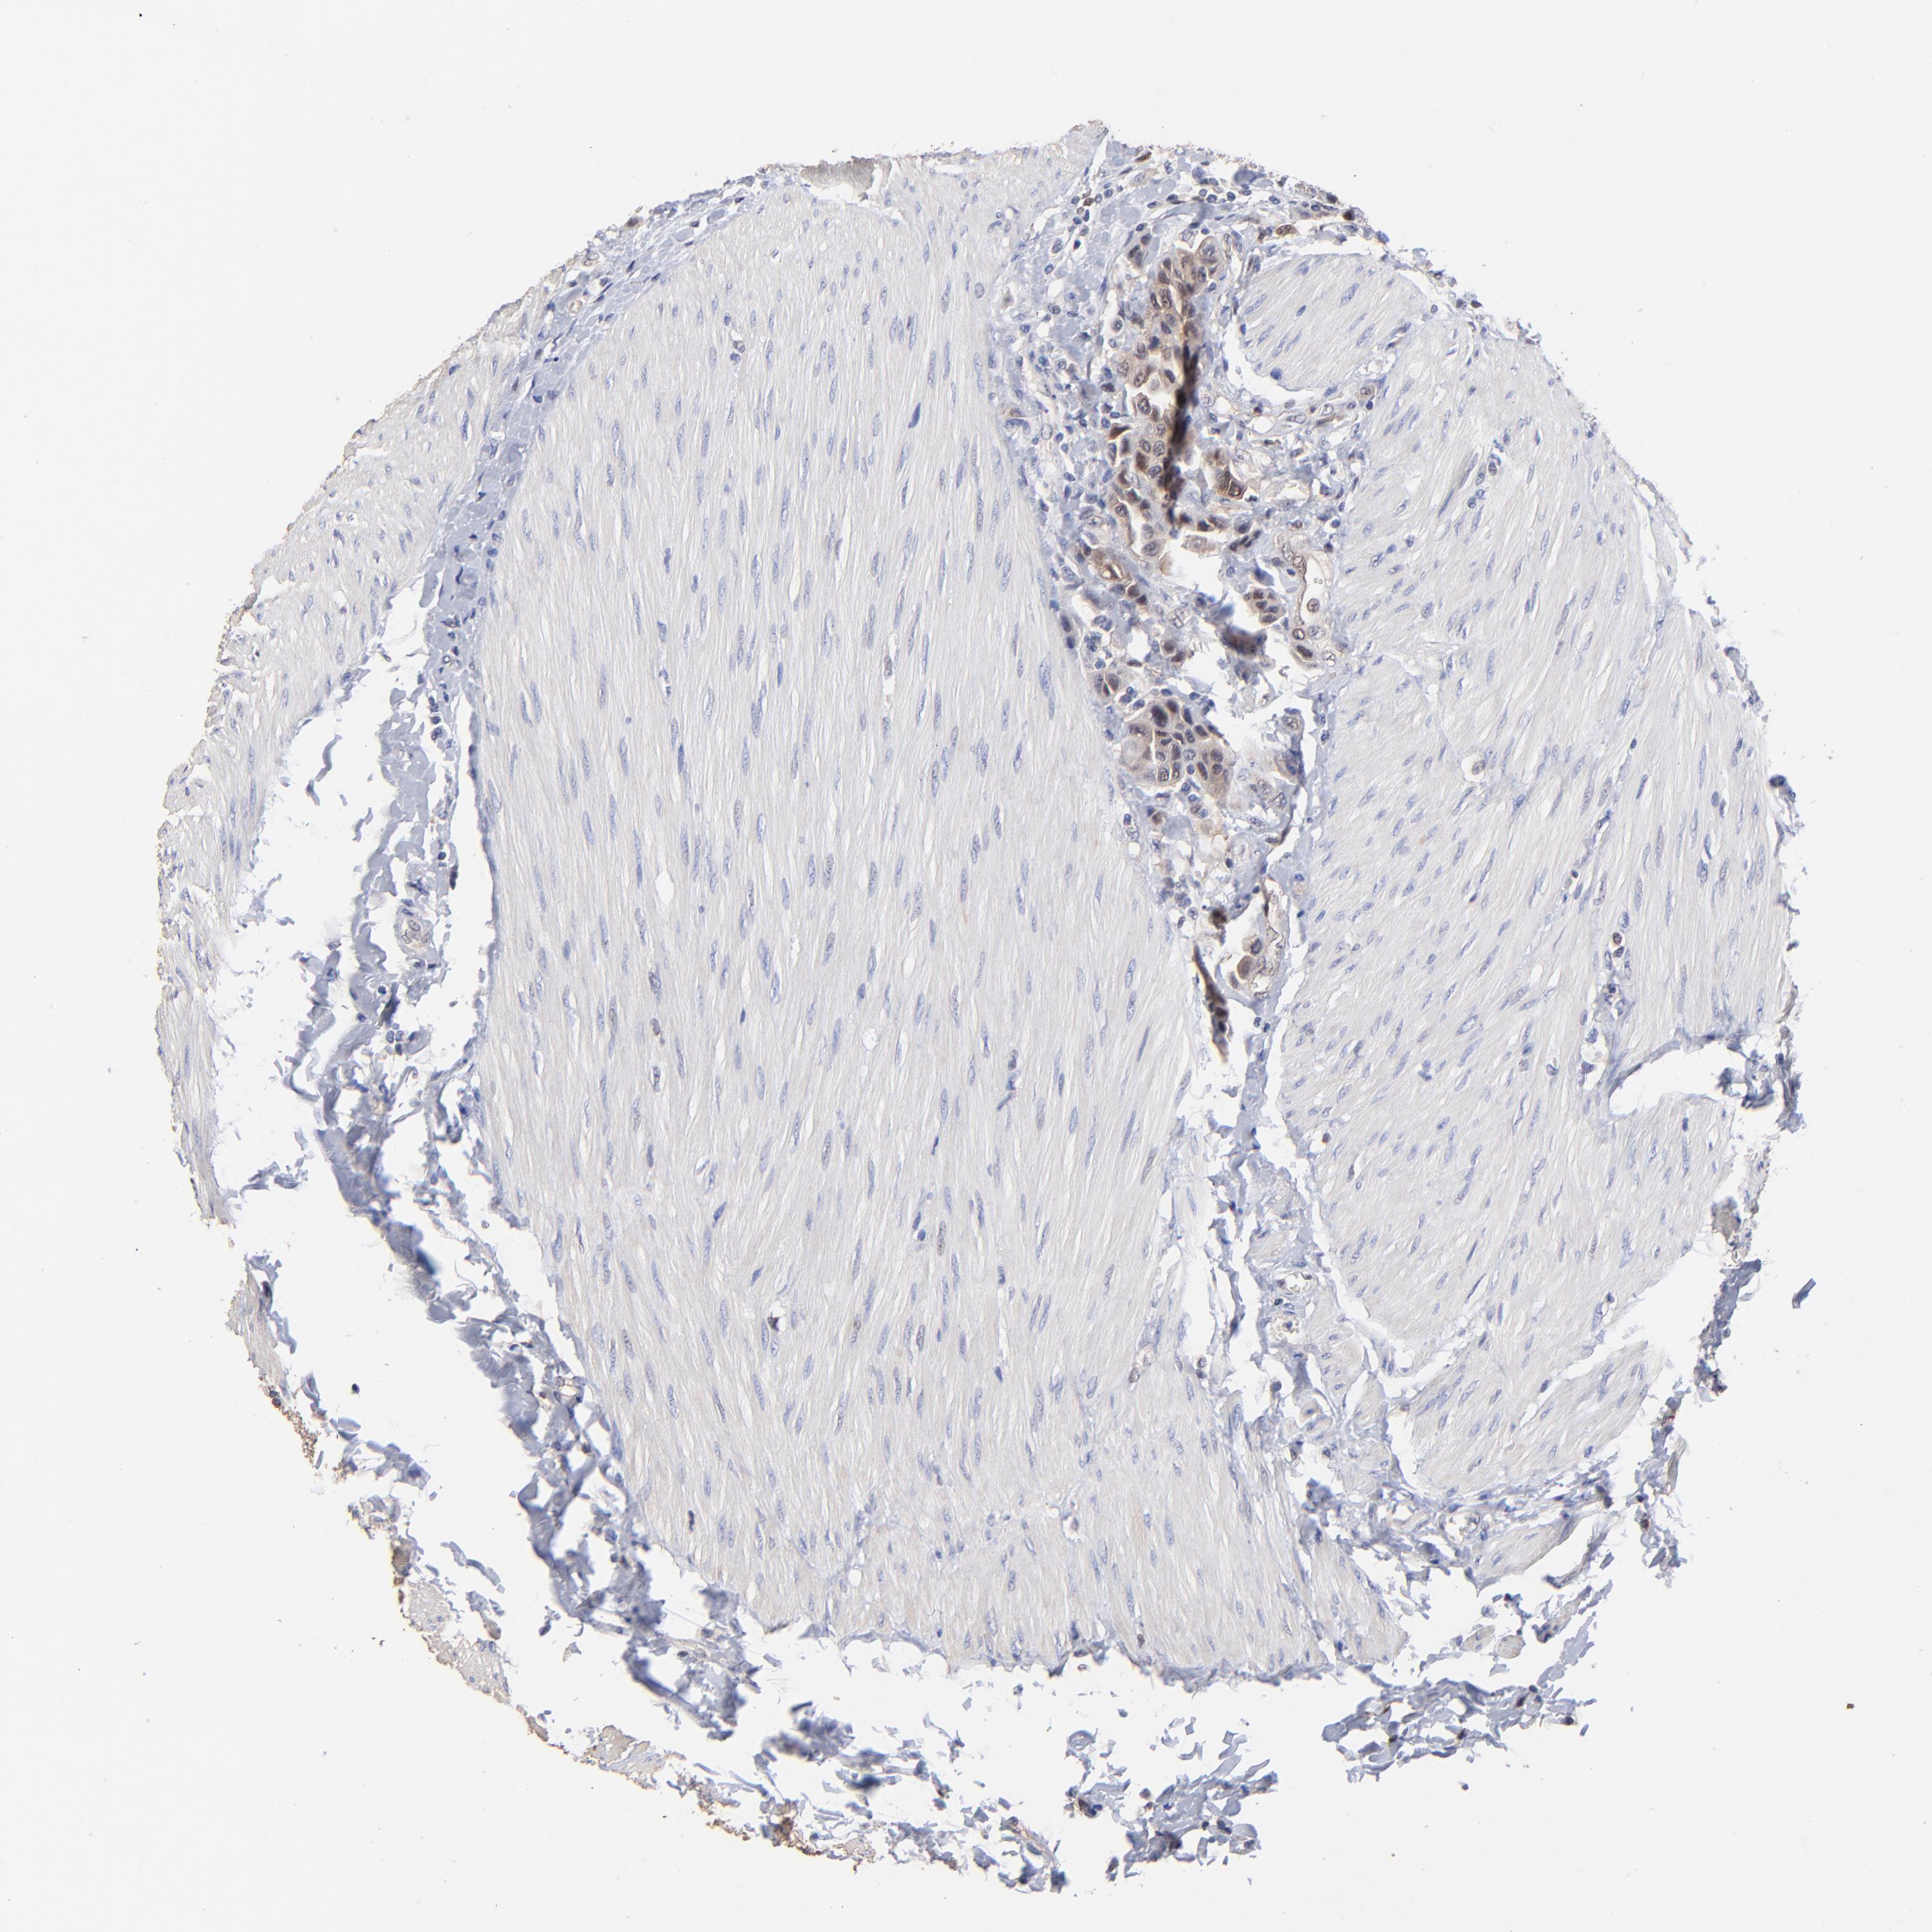

UROTHELIAL CANCER - Protein expressioni

A mouse-over function shows sample information and annotation data. Click on an image to view it in a full screen mode. Samples can be filtered based on level of antibody staining by selecting one or several of the following categories: high, medium, low and not detected. The assay and annotation is described here.

Antibody stainingi

Antibody staining in the annotated cell types in the current human tissue is reported as not detected, low, medium, or high, based on conventional immunohistochemistry profiling in selected tissues. This score is based on the combination of the staining intensity and fraction of stained cells.

Each image is clickable and will lead to virtual microscopy that enables deeper exploration of all samples and also displays staining intensity scores, fraction scores and subcellular localization as well as patient and tissue information for each sample.

Antibody HPA002832

Staining

High

Medium

Low

Not detected

Intensity

Strong

Moderate

Weak

Negative

Quantity

>75%

75%-25%

<25%

None

Location

Nuclear

Cytoplasmic/membranous

Cytoplasmic/membranous,nuclear

Urothelial carcinoma, High grade

Urothelial carcinoma, Low grade